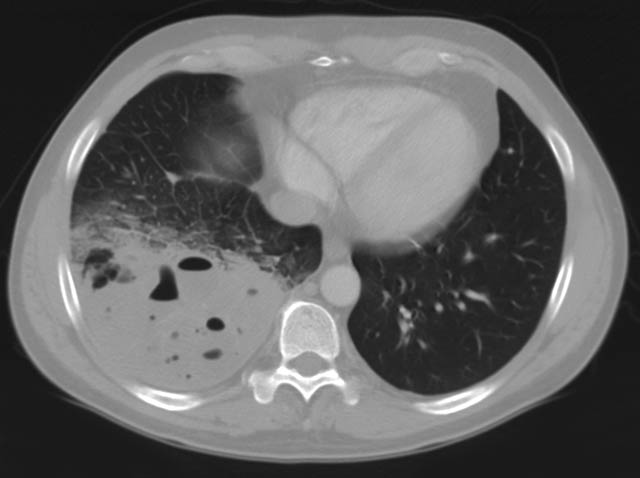

A previously healthy 43-year-old male presented with cough, fevers, and leukocytosis. A chest radiograph (Figure 1) revealed extensive consolidation in the right lower lung containing multiple cavities with air-fluid levels consistent with a necrotizing infection. A chest computed tomogram (Figure 2) showed an abscess cavity and consolidation in the right lower lobe with an aberrant blood supply from the descending aorta. This systemic blood supply was confirmed by subsequent 3D reconstruction (Figure 3). He was initially treated with IV antibiotics, resulting in normalization of his temperature and white blood cell count. He was then discharged home on a 3-week course of oral antibiotics. Three days prior to a planned surgical resection, he underwent angiographic localization of the feeding artery (Figure 4) and coil embolization (Figure 5).

The arterial blood supply to ILS originates from the lower thoracic or upper abdominal aorta, while venous drainage remains normal to the left atrium. Although sequestrations may be diagnosed as early as 18 weeks gestation by ultrasonography, chest radiography is often the first diagnostic step in ILS [5]. They may present as a dense pulmonary mass, sometimes with cystic changes or air-fluid levels from infection. Use of CT angiography has become more prevalent, allowing the characterization of aberrant blood supply, bronchial anatomy, and lung parenchyma [6].